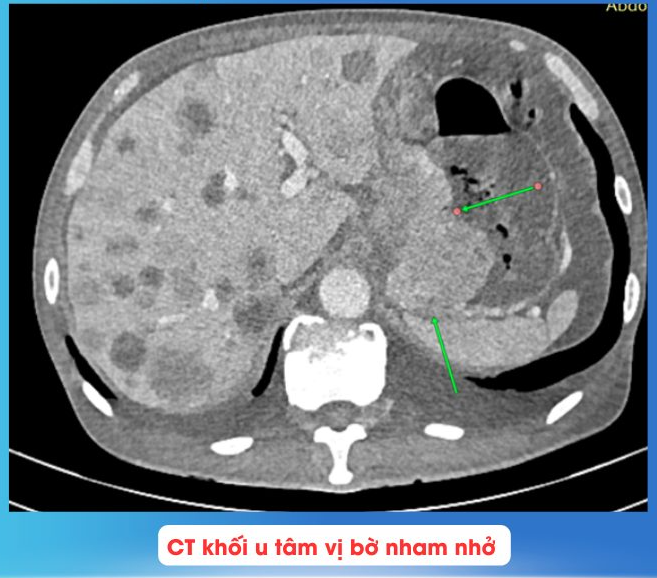

Bệnh nhân C.V.Q (nam, 61 tuổi) nhập viện vì tiêu phân đen, tiền căn ung thư tâm vị dạ dày giai đoạn T4N2M1, di căn phổi – gan – xương (phát hiện từ tháng 6/2025). Bệnh nhân hóa trị được 01 tháng thì ngưng điều trị, sau đó tiếp tục nhập viện và đến nay đã hóa trị đến chu kỳ 4 (FOLFIRI).

Trong quá trình nhập viện, bệnh nhân tiêu phân đen tăng dần, HGB ghi nhận giảm từ 7 -> 3.3 g/dl, BN được chỉ định truyền máu và nội soi dạ dày ghi nhận: sang thương chồi sùi, chiếm hết chu vi chỗ nối thực quản - dạ dày gây hẹp lòng, máy soi không qua được, mô bở, dễ chảy máu, ống soi không tiến xa được thêm.

Kết hợp thăm khám đánh giá, đây là một trường hợp biến chứng xuất huyết nặng do ung thư tâm vị có thể dẫn đến sốc mất máu suy đa cơ quan. Các bác sĩ hội chẩn đã quyết định tiến hành can thiệp cấp cứu tắc mạch khối u dạ dày cầm máu.